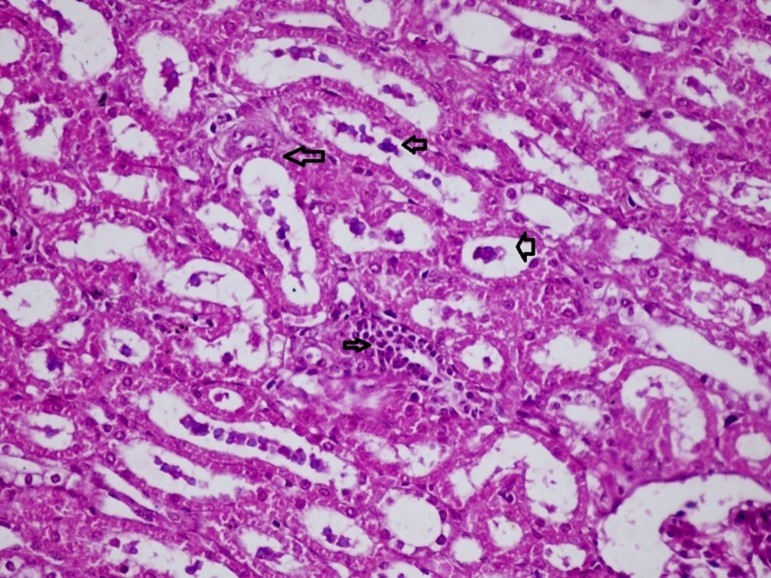

Figures 6.kidneys (dead cattle less than 1 year old) showed severe hydropic degeneration of renal tubular epithelium accompanied by dilated renal tubules, vesicles formations and casts (arrows). (H&E, X 100)

Figures 7.kidneys (dead cattle less than 1 year old) showed severe hydropic degeneration of renal tubular epithelium accompanied by dilated renal tubules, vesicles formations and casts (arrows). (H&E, X 60)